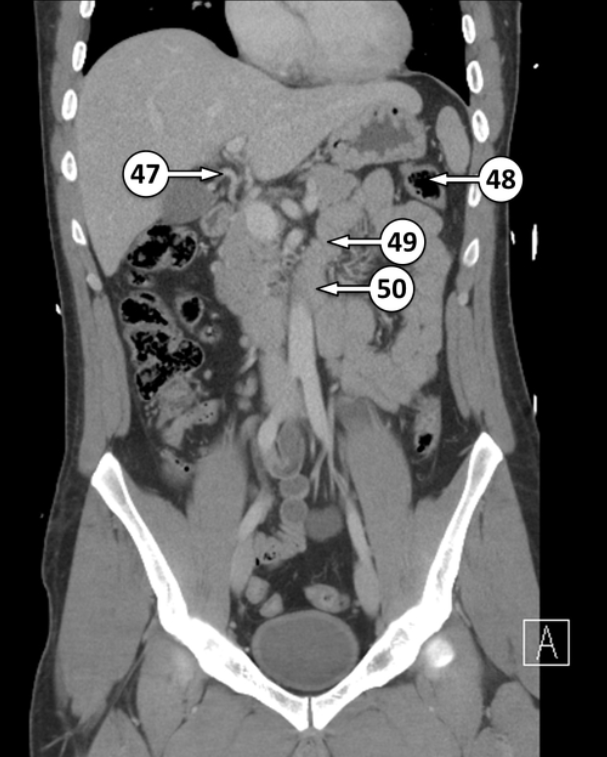

Please label this coronal CT scan

What artery is number 47?

48 and 49 are flexures. Please label the different flexures

Splenic flexure

Duodenojejunal flexure